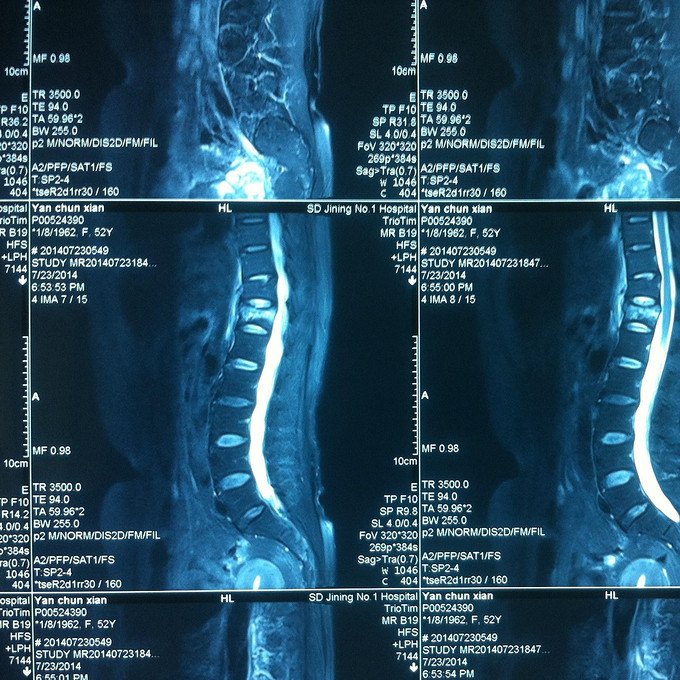

查体:腰部叩痛,腰部活动受限,双下肢感觉无异常,双侧屈髋、伸膝、踝背伸、踇背伸、跖屈肌肌力4-5级,双侧膝腱反射++,跟腱反射+,双侧巴氏征阴性, 影像学检查MR:腰椎骨折,累及中柱。

诊断:腰椎骨折 处理:1、完善相关辅助检查,明确诊断,有无手术指证; 2、患者拒绝行腰椎后路撑开复位内固定术;3、给予绝对卧床,在床上行腰部逐渐加软垫复位,配合促骨愈合、消肿药物。